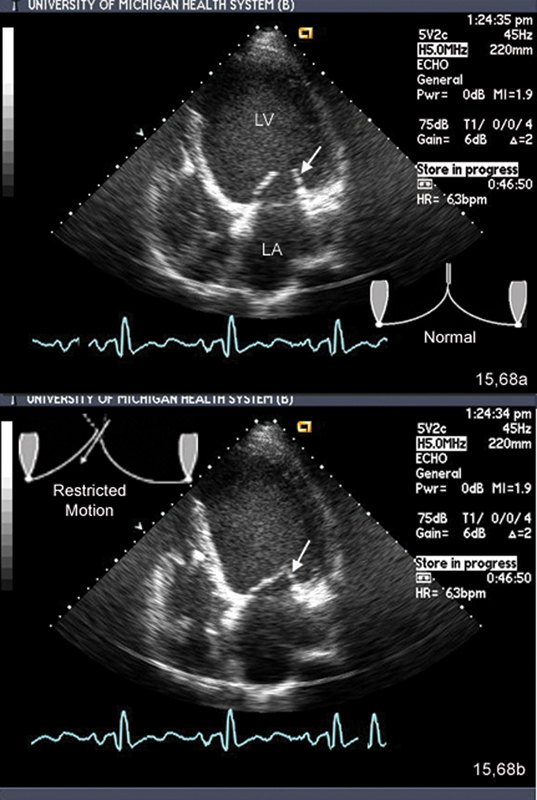

فحوصات تشخيصية لبعض امراض القلب والشرايين التاجية